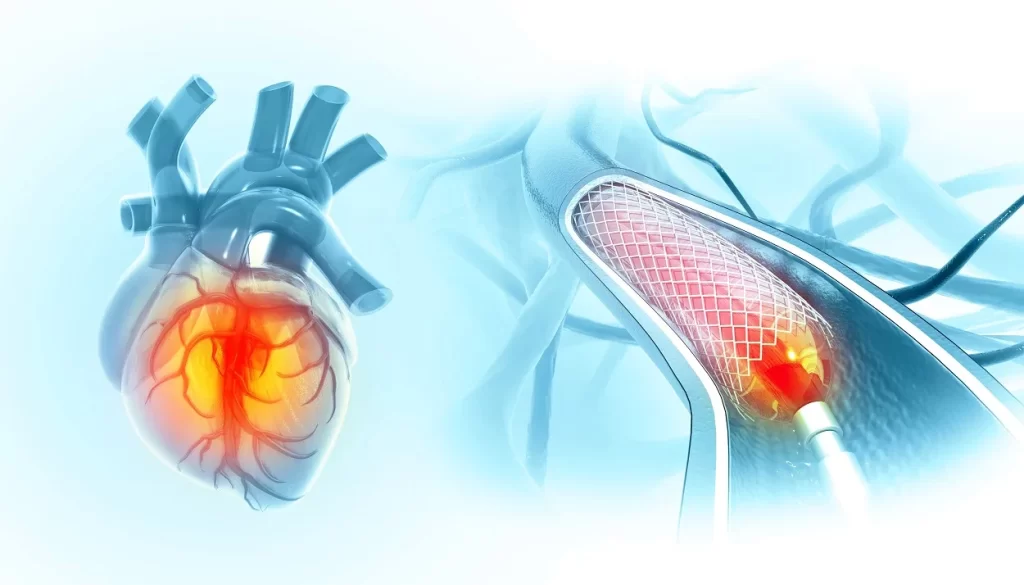

Coronary Angiography and Angioplasty (aka Coronary Catheterization)

A minimally invasive diagnostic and treatment procedure that examines blood flow through your coronary arteries and can restore normal flow when blockages are found.

How it happens: A cardiac catheterization happens in a hospital setting. Our interventional cardiologists insert a thin, flexible tube (catheter) through a blood vessel in your wrist or groin and guide it to your heart. A special dye is injected to make your arteries visible on X-ray screens. If blockages are found, tiny balloons can inflate to widen the artery, and mesh tubes called stents may be placed to keep the artery open.

When it’s necessary: We may recommend this procedure if you have symptoms of coronary artery disease, abnormal stress test results, or to evaluate chest pain that could indicate blocked arteries.